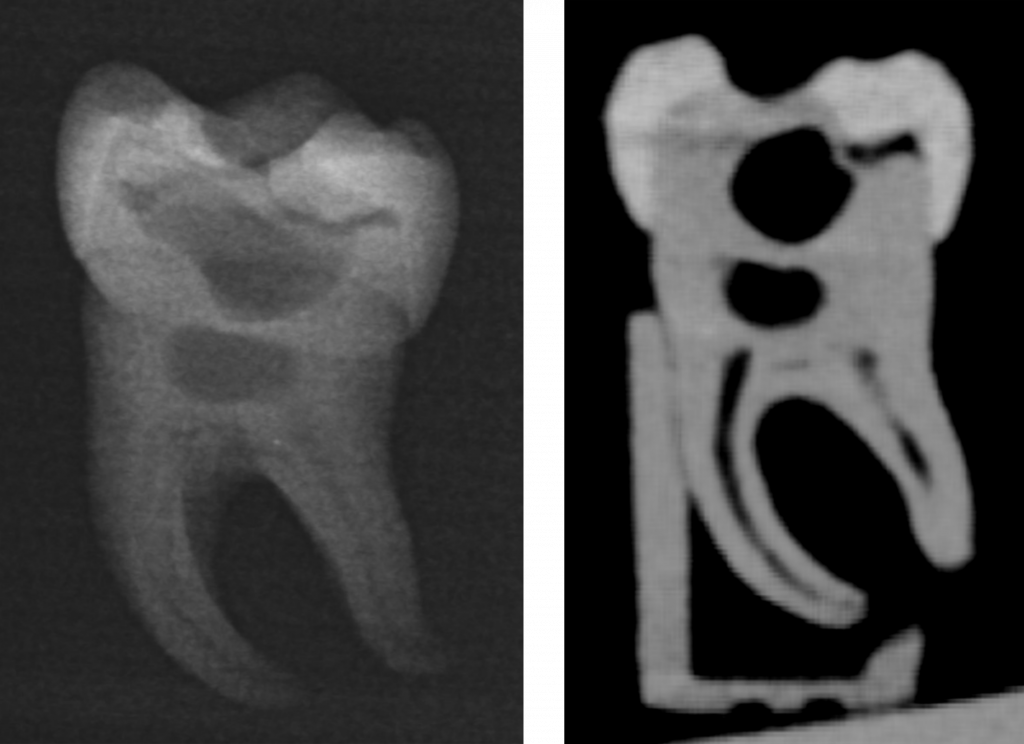

Der gedruckte Zahn besitzt ein realistisches Röntgenverhalten. Links Aussehen des Zahnes bei einem Zahnfilm mit allen erkennbaren Innenstrukturen und rechts bei einer dreidimensionalen Röntgenaufnahme in Form eines so genannten DVT´s. Bild: Christian Höhne / UKW

dem ärztlichen Direktor der Poliklinik für Zahnärztliche Prothetik, für die vorklinische Lehre der Abteilung zuständig. Neben seinem Zahnmedizinstudium und seiner Habilitation zum 3D-Druck in der Zahnmedizin hat Höhne Wissen im Bereich des Maschinenbaus erworben, hierbei vor allem in der Konstruktion und Herstellung von Prototypen sowie Nanostrukturtechnik. Bereits im Jahr 2019 hatte er basierend auf einer dreidimensionalen Röntgenaufnahme eines kariösen Zahnes einen ersten 3D-gedruckten Zahn hergestellt. Um den harten Zahnschmelz, das darunterliegende Dentin, die kariöse Substanz und den empfindlichen Zahnnerv (Pulpa) realistisch darzustellen, verwendete er unterschiedliche Materialien mit verschiedener Härte. So erhielten die Studierenden beim Bohren durch die entsprechenden Schichten eine taktile Rückmeldung, ähnlich wie bei einem natürlichen Zahn. Sie konnten somit praxisnah üben, wann sie stoppen oder vorsichtiger arbeiten müssen. Die im Journal of Dental Education publizierte Studie zeigte, dass 3D-gedruckte Zähne eine vielversprechende Alternative zu klassischen Modellzähnen darstellen.